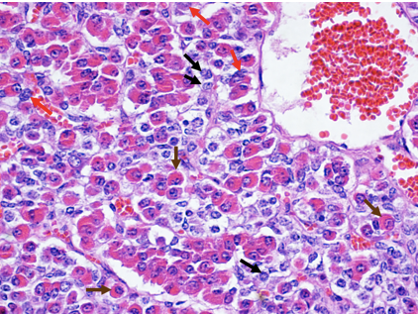

Chromophobes –> black arrows

Acidophils –> brown arrows

Basophils –> red arrows